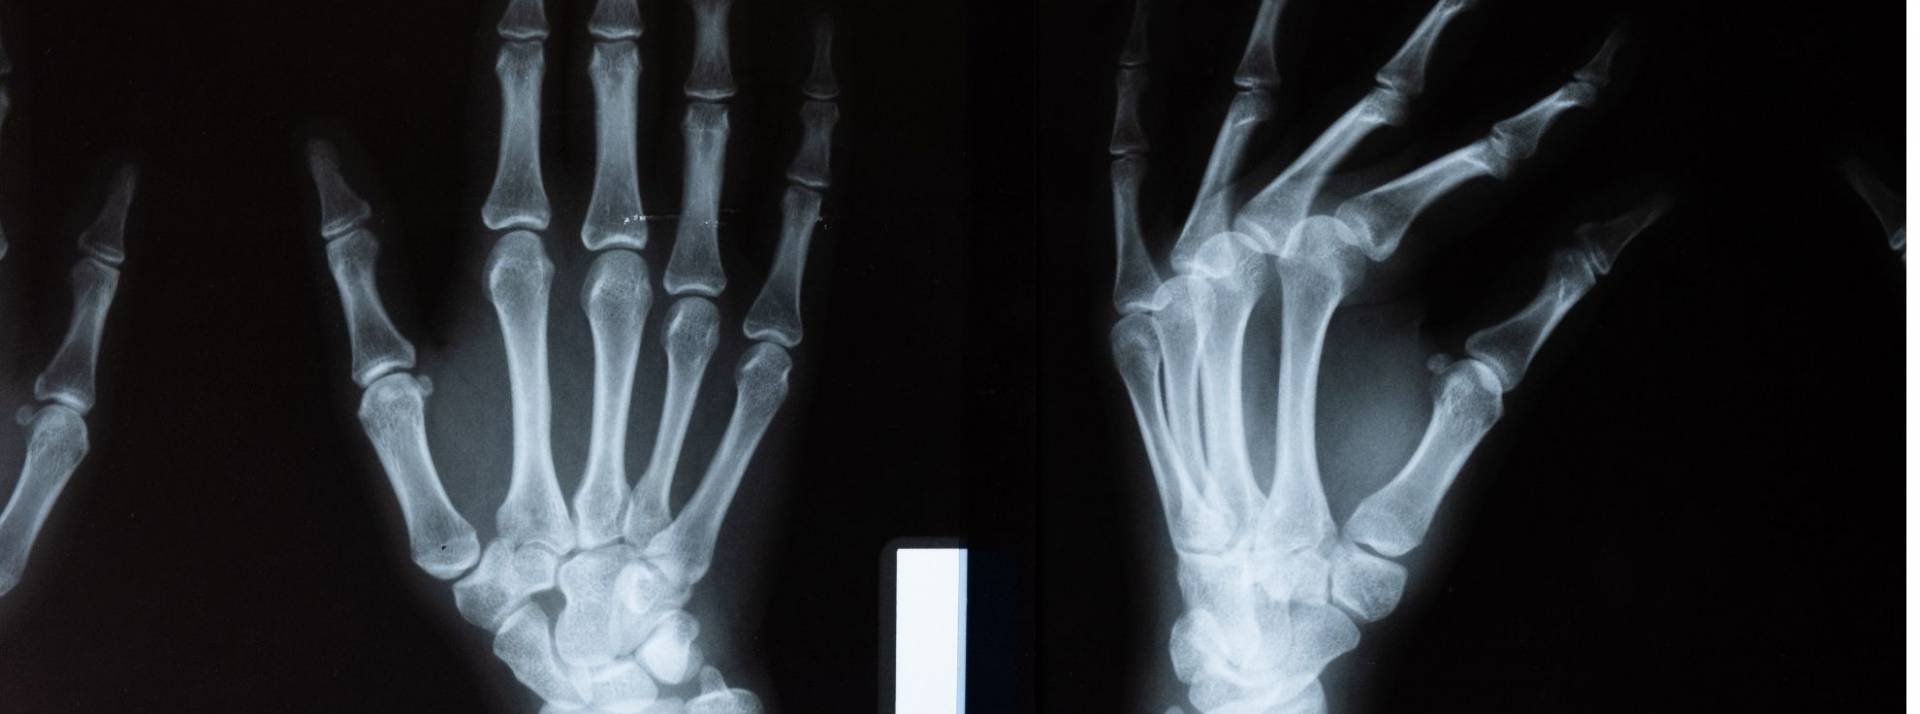

Après plusieurs années de R&D et de validation clinique, Milvue a développé et certifié en 2020 une IA analysant les radiographies grâce au « deep learning » . La Milvue Suite facilite le travail au quotidien des radiologues et des cliniciens, en priorisant les images et en fournissant un premier diagnostic.